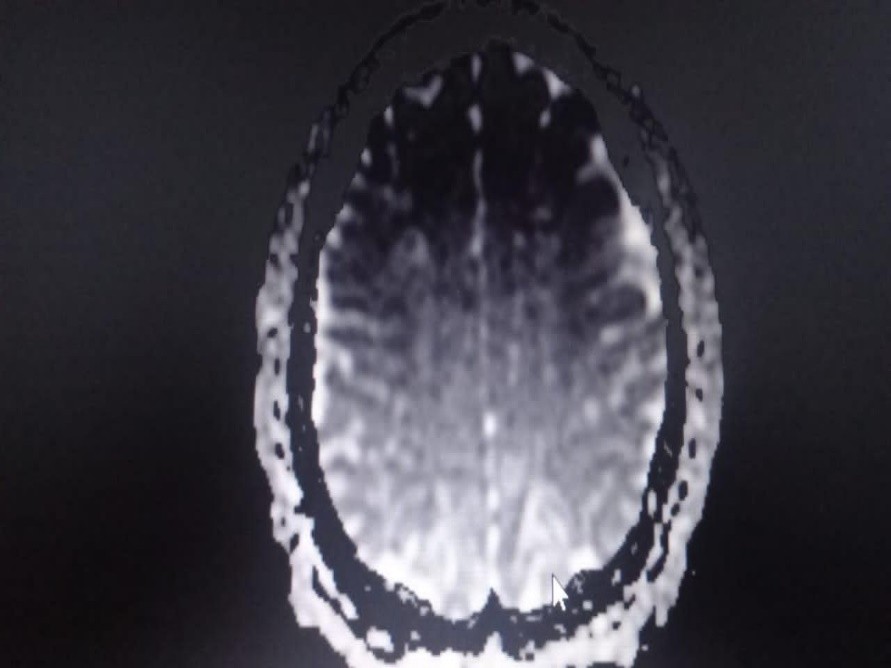

Radiologiquement, l’examen clef pour poser ce diagnostic est l’IRM cérébrale (11). Le scanner cérébral réalisé initialement avait été non contributif. La littérature rapporte que la TDM cérébrale est un moyen de diagnostic mais moins sensible. Elle peut être normale comme observée chez notre patiente, ou montrer des lésions hypodenses cortico-sous-corticales. Typiquement, l’IRM retrouve des anomalies corticales et sous-corticales d’oedème vasogénique (en hyper-signal T2 et FLAIR) prédominantes dans les régions pariéto-occipitales (figures 1 et 2).

Figure2 : IRM Cérébrale : Hypersignal ADC pariétal occipital bilatéral symétrique.